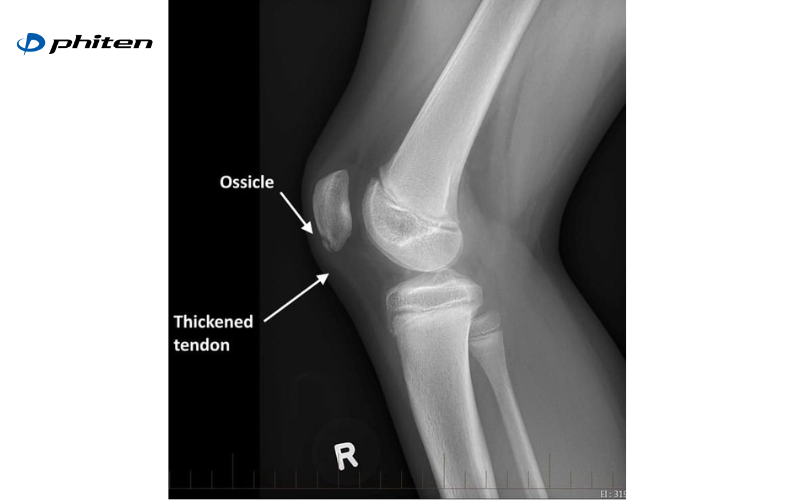

- Chụp X-quang: Giúp đánh giá cấu trúc xương, phát hiện bất thường về hình dạng khớp hoặc dấu hiệu thoái hóa sớm

- Chụp CT hoặc MRI: Cho hình ảnh chi tiết về mô mềm, gân, dây chằng, sụn chêm và màng hoạt dịch, từ đó phát hiện các tổn thương mà X-quang không thể hiện rõ